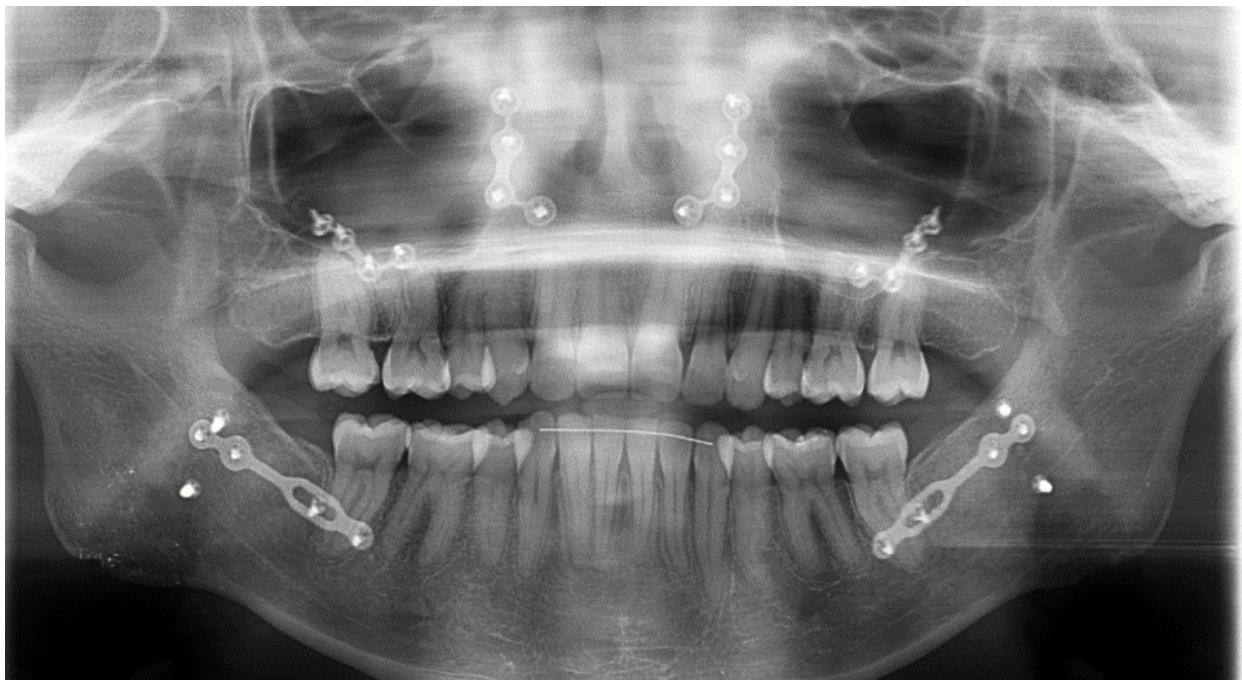

Orthopantomographie prise lors de la mise en traction du système. Les ressorts sont connectés entre les Abalakov et les canines mandibulaires en traction directe.

Examen orthopantomographique de fin de traitement